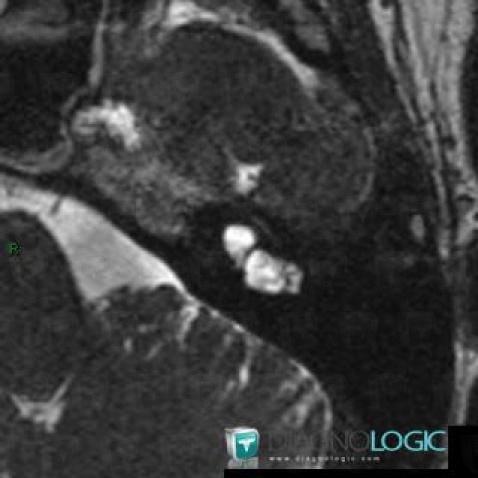

Voici les informations spécifiques à l'image clé ci dessus:

- Diagnostic Dysplasie cochléaire, Localisation(s) Oreille interne, comportant les gammes Lésion de l'oreille interne